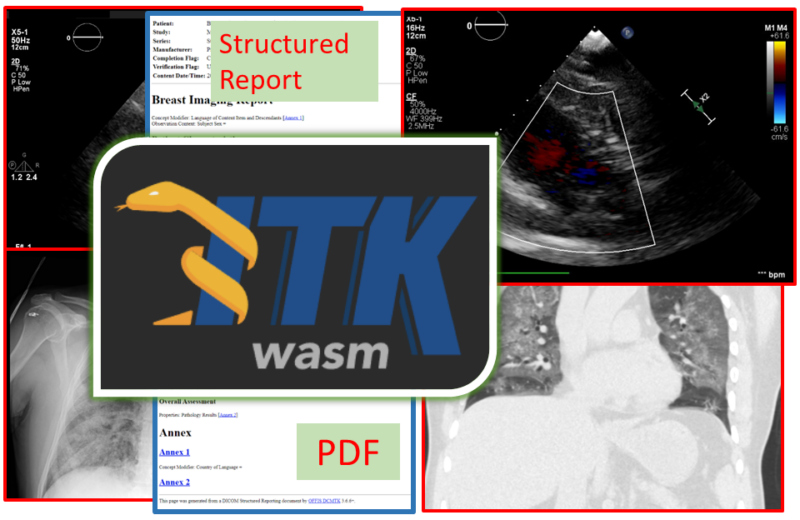

Enhance care with our medical Python Library Rt Dicom Monaco gallery of comprehensive galleries of therapeutic images. medically documenting photography, images, and pictures. designed to support medical professionals. Discover high-resolution Python Library Rt Dicom Monaco images optimized for various applications. Suitable for various applications including web design, social media, personal projects, and digital content creation All Python Library Rt Dicom Monaco images are available in high resolution with professional-grade quality, optimized for both digital and print applications, and include comprehensive metadata for easy organization and usage. Discover the perfect Python Library Rt Dicom Monaco images to enhance your visual communication needs. Our Python Library Rt Dicom Monaco database continuously expands with fresh, relevant content from skilled photographers. Instant download capabilities enable immediate access to chosen Python Library Rt Dicom Monaco images. Diverse style options within the Python Library Rt Dicom Monaco collection suit various aesthetic preferences. The Python Library Rt Dicom Monaco archive serves professionals, educators, and creatives across diverse industries. Regular updates keep the Python Library Rt Dicom Monaco collection current with contemporary trends and styles. Comprehensive tagging systems facilitate quick discovery of relevant Python Library Rt Dicom Monaco content. Time-saving browsing features help users locate ideal Python Library Rt Dicom Monaco images quickly.